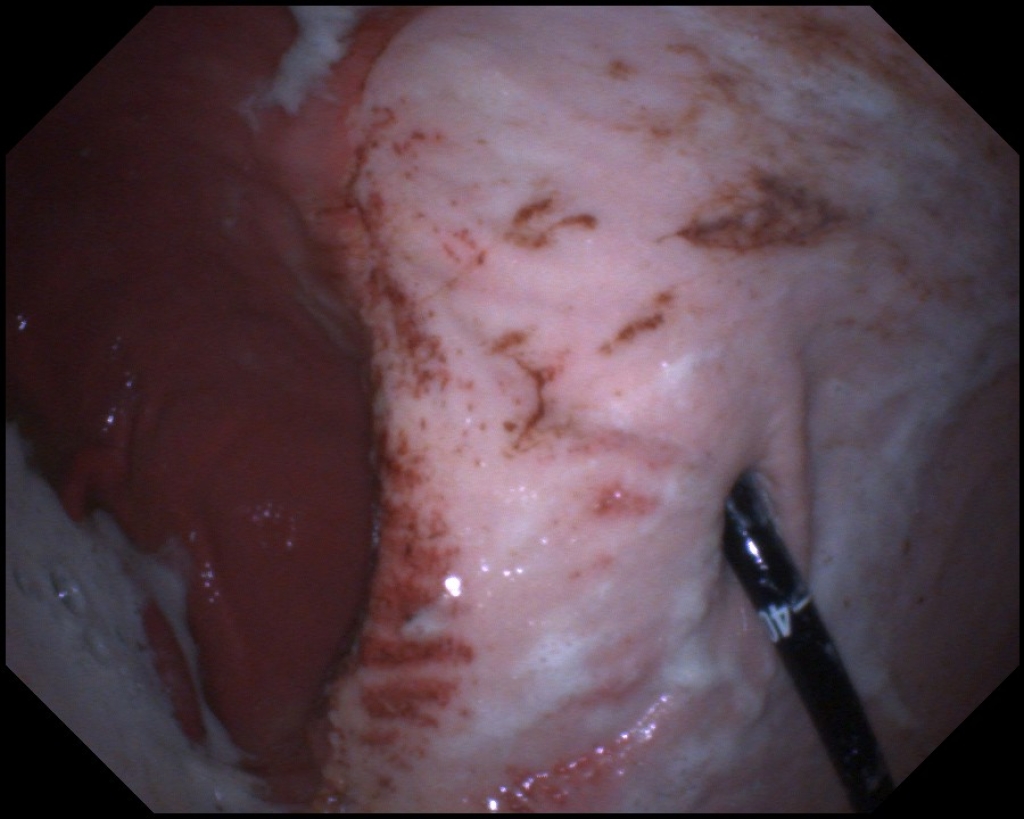

Maagulcera in het onderste gedeelte van de maag zien we wat minder vaak en zijn moeilijker om te behandelen. Ondanks wetenschappelijk onderzoek weten we  eigenlijk nog niet goed waarom  deze maagzweren ontstaan. Bij mensen komen vergelijkbare maagzweren voor, deze zijn veelal het gevolg van medicijn gebruik of een bacteriële infectie van de maagwand. Bij paarden is wel uit onderzoek gebleken dat bacteriën geen grote rol spelen in het ontstaan. Ook hebben veel paarden met dit type maagzweren geen medicijnen gebruikt die dit kunnen veroorzaken. Wat de achterliggende oorzaak is voor het ontstaan van deze zweren is dus nog niet goed bekend. Overigens is bij 30% van de maagzweren bij mensen de oorzaak ook niet bekend. Dit maakt dat deze maagzweren vaak lastiger te behandelen zijn en een langdurige behandeling vergen.

Links: Diepe maagzweren in het onderste gedeelte van de maag

Rechts: Maagzweren onderin de maag rondom de uitgang naar de dunne darm

Diepe maagzweren in het onderste gedeelte van de maag

Maagzweren onderin de maag rondom de uitgang naar de dunne darm